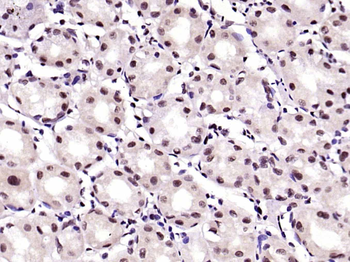

50 μl, 100 μl - KLF4 Recombinant Rabbit Monoclonal Antibody [orb608075]Featured